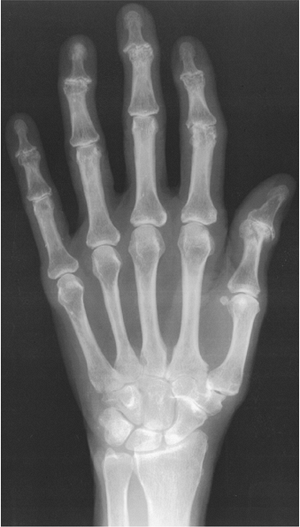

FIGURE 9-41

Enchondromas. PA radiograph of the hand demonstrating multiple lytic expanding lesions in the second metacarpal and second and third phalanges. |